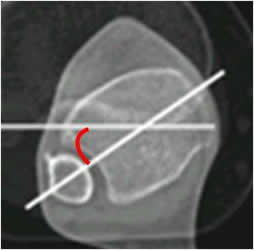

Angulo de rotación de la rodilla:

Medido mediante TAC, con cortes axiales que se superponen. Uno sobre los cóndilos femorales y otro sobre la tuberosidad tibial. (22).

El ángulo se forma por las líneas bicondilea posterior y otra que pasa por la parte

posterior de la epífisis tibial. El valor normal es de 5º. (3, 18, 22). (Fig 78 y 79).

Fig 78. Rotación de la rodilla.

A: TAC axial, con línea que pasa por la parte posterior de los cóndilos femorales.

B: TAC axial a nivel de la espina tibial y se traza la línea que pasa por la parte posterior de la tibia.

Se superponen y forman el ángulo de rotación de la rodilla.

Fig 79. Rotación de la rodilla.

Medición del ángulo con el software de la máquina.